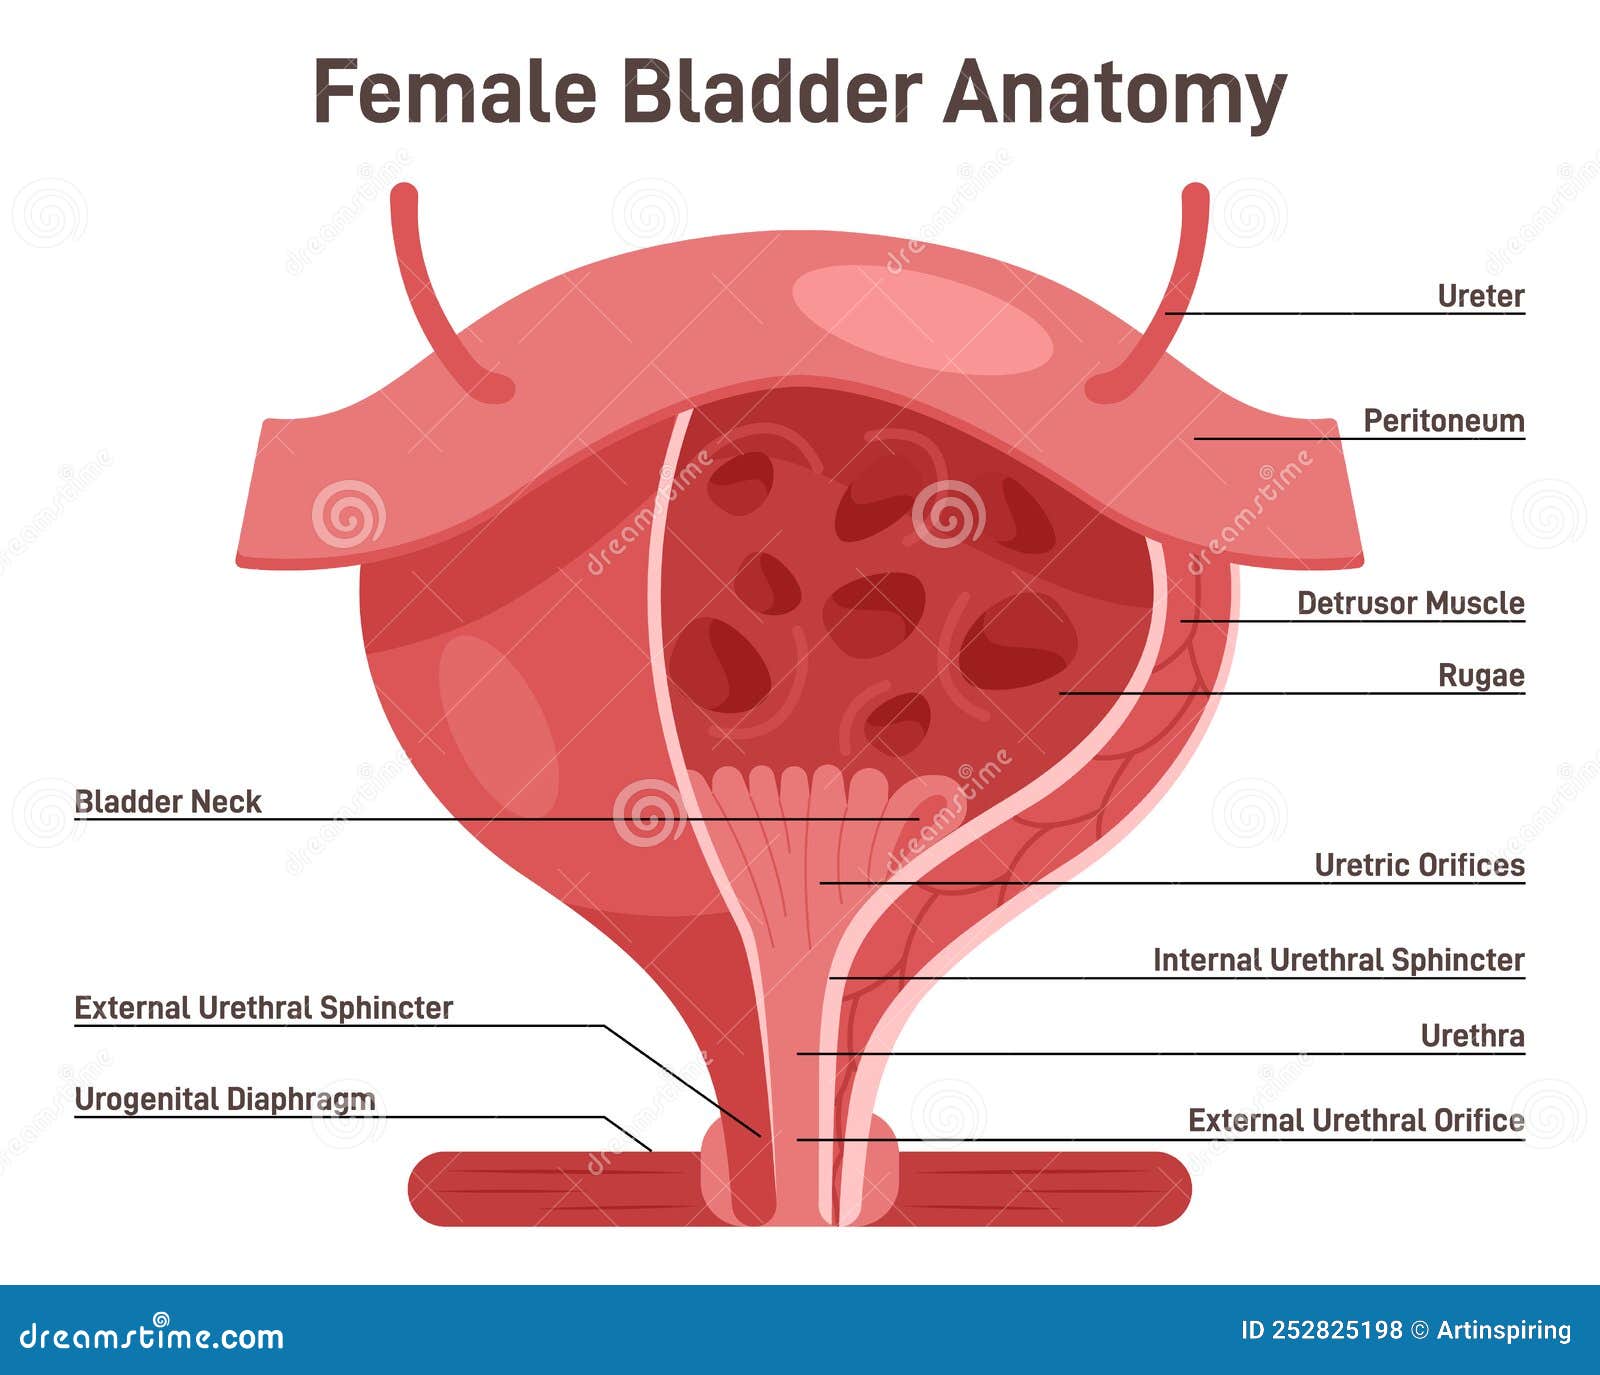

location of the bladder in the human body

Posts: location of the bladder in the human body